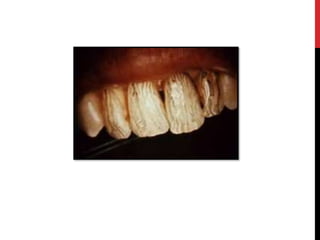

DIFFERENTIAL DIAGNOSIS

Extrinsic disorders, chronological disorders & localised disorders

considered in D/D.

 Commonest D/D  Dental Fluorosis.

 Dentinogenesis imperfecta.

 Molar incisor hypominerilization.

 Gunther disease.

 Hyperbilirubinemia-related discolouration.

 Tetracycline-related discolouration.

• #58 Extrinsic disorders of tooth formation, chronological disorders of tooth formation and localised disorders of tooth formation should be considered in the differential diagnosis. The commonest differential diagnosis is dental fluorosis. The variability of this condition, from mild white "flecking“ of the enamel to profoundly dense white colouration with random, disfiguring areas of staining and hypoplasia, requires careful questioning to distinguish from AI. Fluorosis may present with areas of horizontal white banding corresponding to periods of more intense fluoride intake and may show the premolars or second permanent molars to be spared (chronological distribution). DIFFERENTIAL DIAGNOSIS The eruption of teeth that are discolored or that soon become discolored suggests fluorosis or dentinogenesis imperfecta. Fluorosis may be clinically difficult to distinguish from amelogenesis imperfecta, but family history and testing of water sources can separate the two. In addition, teeth affected by amelogenesis imperfecta have soft enamel, whereas teeth affected by fluorosis have a hardened enamel. Amelogenesis imperfecta is best separated from dentinogenesis imperfecta by examination of the enamel, which will be pitted, globular at the incisors, and clinically soft. The radiographs will show normal pulp chambers in amelogenesis imperfecta, which in dentinogenesis imperfecta are usually obliterated.